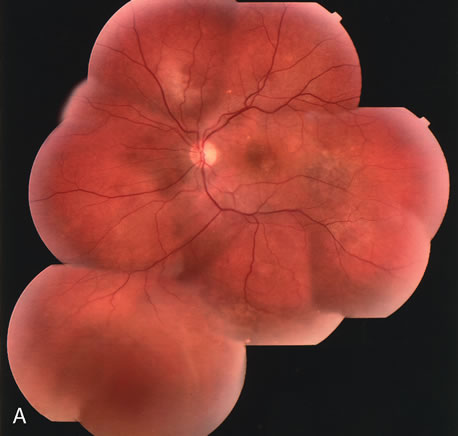

Clinically discernible peripheral dependent bullous neurosensory detachments have been described in patients with chronic CSC.85–92 Yannuzzi and co-workers first characterized the presence of RPE atrophic tracts extending inferiorly in the fundus periphery secondary to antecedent retinal detachment in patients with CSC.85 Presumably, there is a particularly severe and/or longstanding leakage of fluid from an RPE defect in the subretinal space at the posterior pole. The subretinal fluid gravitates inferiorly to form a dependent neurosensory detachment in a “flask,” “teardrop,” “dumbbell,” or “hourglass” pattern (Fig. 31). Sometimes the tract of subretinal fluid connecting the macular detachment with the bullous neurosensory detachment in the inferior hemisphere is so shallow that it is very difficult to appreciate. The RPE under the chronic retinal detachment experiences atrophic changes that appear as atrophic RPE tracts connecting the posterior pole with the dependent retinal detachment. The retina itself develops secondary manifestations including pigment migration, capillary dilatation (telangiectasia) proximally and capillary nonperfusion (ischemia) distally to the area of detached retina (see Fig. 31). The changes in the RPE consist of both RPE atrophy and pigment clumping in the form of perivascular deposits or bone spicules, a condition described by Gass as a “pseudoretinitis pigmentosa–like atypical CSC presentation.”87

Other complications noted in these patients are cystoid macular edema or, more frequently, cystoid retinal changes in the areas of chronic detachment, subretinal lipid deposition, choriocapillaris atrophy secondary to the RPE damage in the areas of RPE tracts, and CNV.89,90,204–206 This severe variant of CSC appears to be more frequent in patients of Latin or Asian ancestry, and it is usually associated with frequent recurrences, permanent central vision loss, and significant superior visual field loss. |